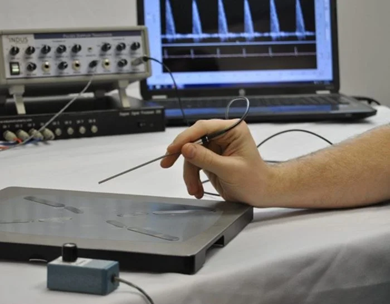

Image Credit: Scintica Instrumentation Inc.